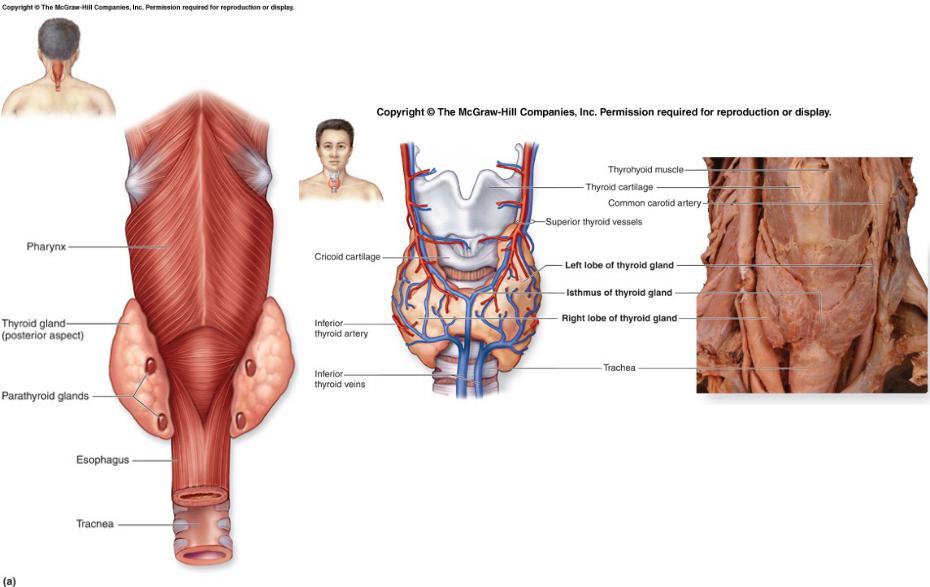

Иллюстрации и схемы по остеопорозу и паращитовидной железе